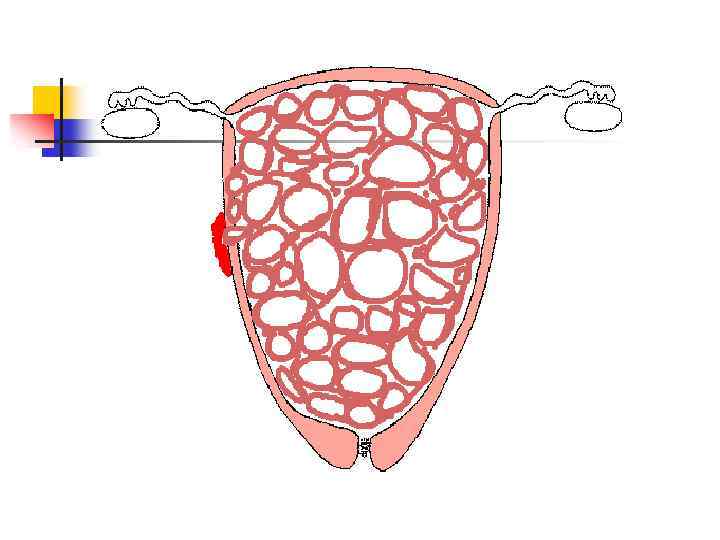

Аденомиоз

Опухоли эндометрия n Полипоз (доброкачественное, предраковое заболевание) n РАК - рост экзо- и эндофитный Гистологическиаденокарциномы и недифференцированные раки n

ОПУХОЛИ МИОМЕТРИЯ n n ДОБРОКАЧЕСТВЕННАЯ – ЛЕЙОМИОМА, ФИБРОМИОМА ЗЛОКАЧЕСТВЕННЫЕ – САРКОМЫ.